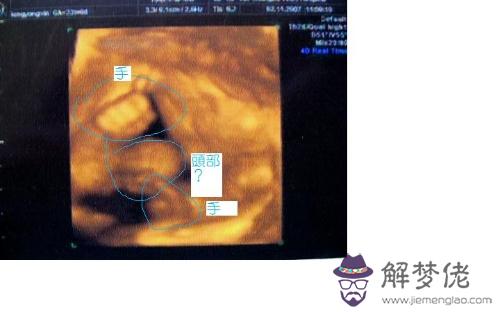

B超看男女準確率有多大?系統彩超看男女。

百分八十,是等你做四維的時候,就比較準確了~~系統b超可以看男女嗎。

但是沒有人會說百分百,~~

如果是懷孕4個月去醫院做彩超,B超醫生一般是可以看得到,如果是看到,就可以完全確定是男孩,現在一般都不 問看,因為看有誤差。當然如果你覺得有誤差,還可以再去做一次彩超復查,一般 答來說懷孕4個月做彩超檢查,還是比較準確的,目 回前建議也不要過分緊張,孩子生出來就 答自然知道孩子的性別。